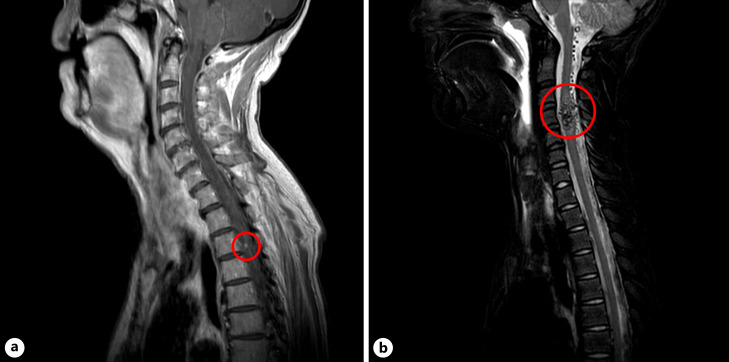

Results: 52.1% were diagnosed with perimesencephalic SAH, 35.0% with non-perimesencephalic, SAH and 12.9% with CT-negative SAH (diagnosed by lumbar puncture). Additional magnetic resonance imaging (MRI) identified a spinal bleeding source in 4 patients (2.86%). These patients presented with local spine pain or neurological deficits (relative risk: 3.9706 [95% confidence interval [CI]: 0.7272-21.6792]; p < 0.001) and were younger (mean difference 14.85 years [95% CI: 0.85-28.85; p = 0.038]) compared to patients without a spinal bleeding source.

Conclusions: AN-SAH caused by spinal pathology is rare. This study indicates that craniocervical and holospinal MRI should be considered in AN-SAH, especially for young patients with AN-SAH who present with back pain or neurological deficits.